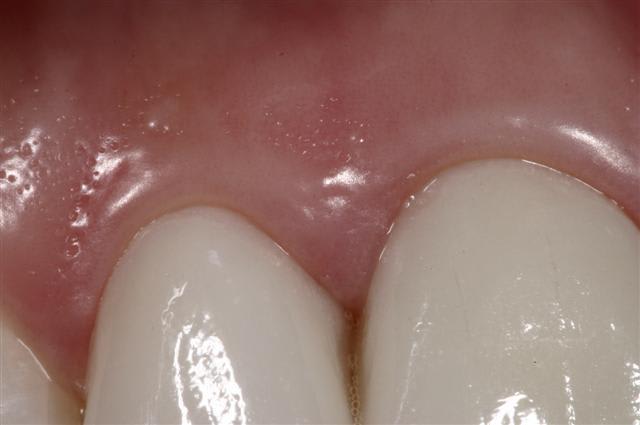

Quattres Empress 2...

et collées ...

Reste un peu de colle :)

Il y a eu blanchiment

Pour info les compo avaient des vis intra dentinaire.. Encore un qui croyait pas dans le collage..